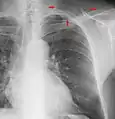

- Chest film showing increased opacity in both lungs, indicative of pneumonia